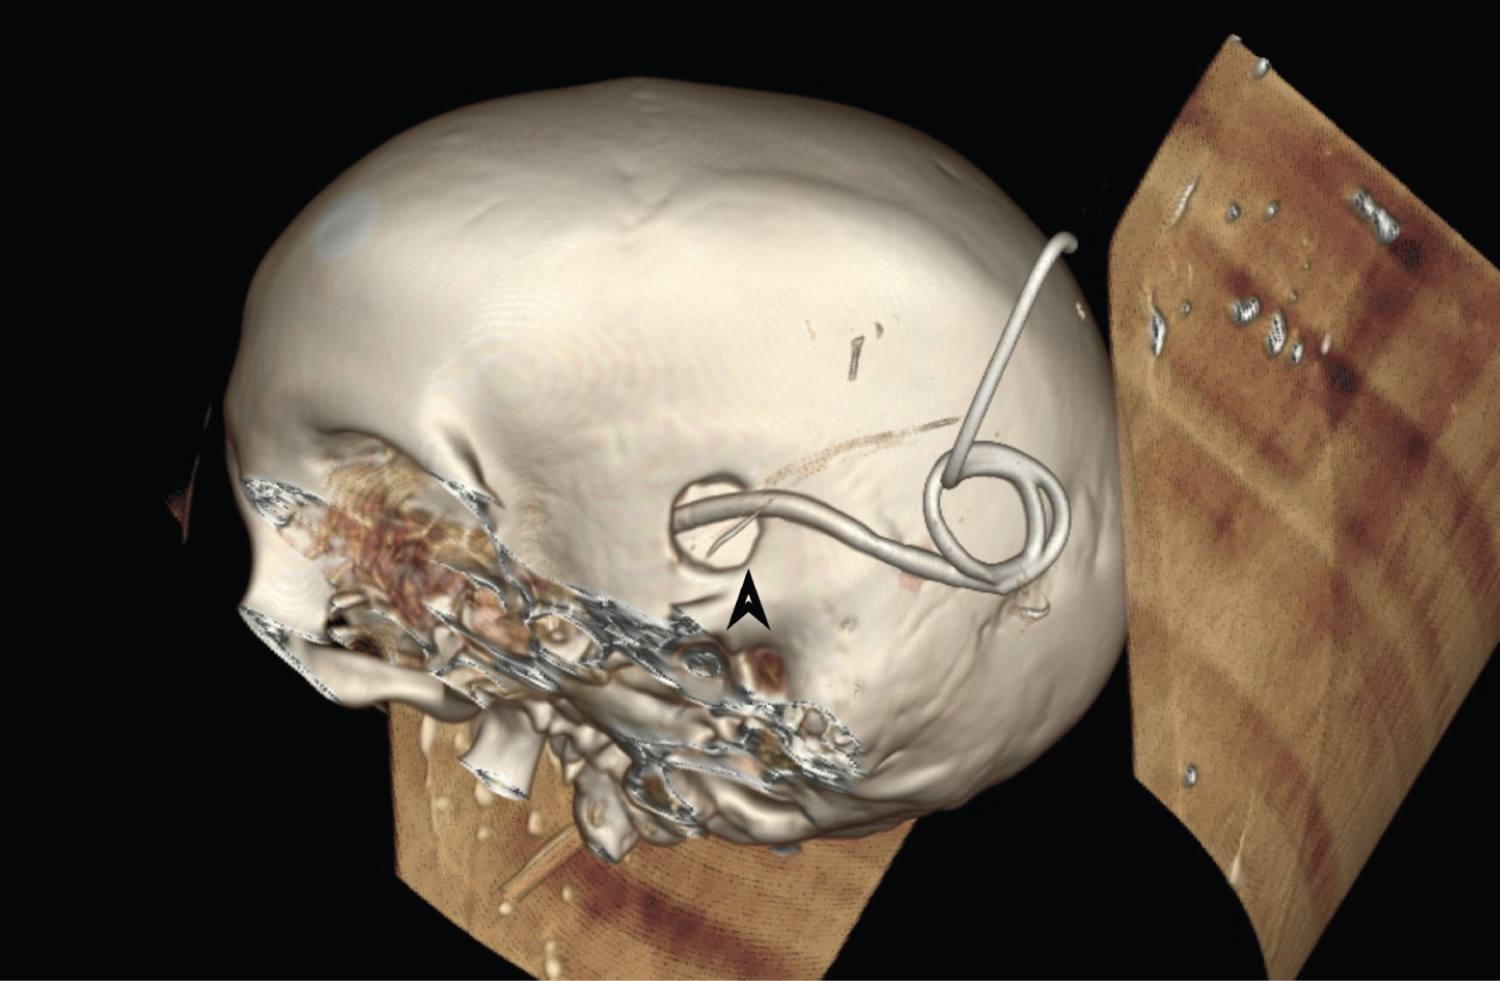

A 33-year-old female was admitted to COVID ICU after testing positive for the disease with 7 days history of fever, cough, inability to open as well as pain in the left eye, and inability to speak with right sided hemiparesis. She was known diabetic and hypertensive. Clinical examination showed presence of multiple pus points in left infratemopral region. Its microscopic examination showed wide area of necrosis along with cluster of mucormycosis. Due to sudden deterioration of patients GCS, CECT head was done (Figure 1) which showed multiple irregular thick walled peripherally enhancing lesion involving the left frontal, parietal and basal ganglia. It also showed presence of significant perilesional edema causing mass effect and midline shift (Figure 1). Patient underwent emergency debridement and burr hole drainage of abscess along with placement of external ventricular drain (Figure 2). The possible mechanism could be that the fungus has gained access to the brain from orbit or paranasal sinus resulting in sequential involvement and abscess formation. Gradually, patient condition deteriorated with progression of disease and she died due to refractory shock and extensive brain involvement.

Figure 1: CECT head showing multiple irregular thick walled (green) peripherally enhancing lesion (red arrow) along with fronto-temporo-parietal infarct (blue arrow) with mass effect and midline shift.